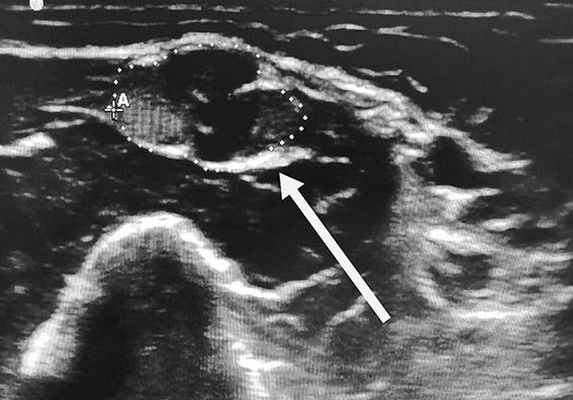

Если данных для установки диагноза окажется недостаточно, могут дополнительно проводиться МРТ сплетений, анализ спинномозговой жидкости, УЗИ периферических нервов и в редких случаях биопсия нерва. К одним из критериев правильности установленного диагноза относится улучшение состояния, либо приостановление прогрессирования заболевания на фоне патогенетической терапии.